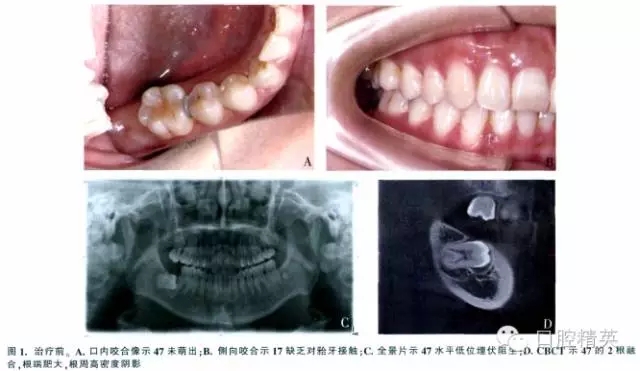

女,37歲,右下頜埋伏牙,要求治療。檢查示面型對稱,側(cè)貌正常。47未萌,17腭尖下垂,其余牙咬合好(圖1A、B)。全景片示:47水平低位埋伏,47冠方有一不完整的透明陰影,周圍呈現(xiàn)白色反應線,根方有致密陰影(圖1C)。錐形束CT(CBCT)示47接近水平位,牙長軸與牙合平面前上方夾角約為75°,根尖端肥大,牙周膜間隙模糊(圖1D)。